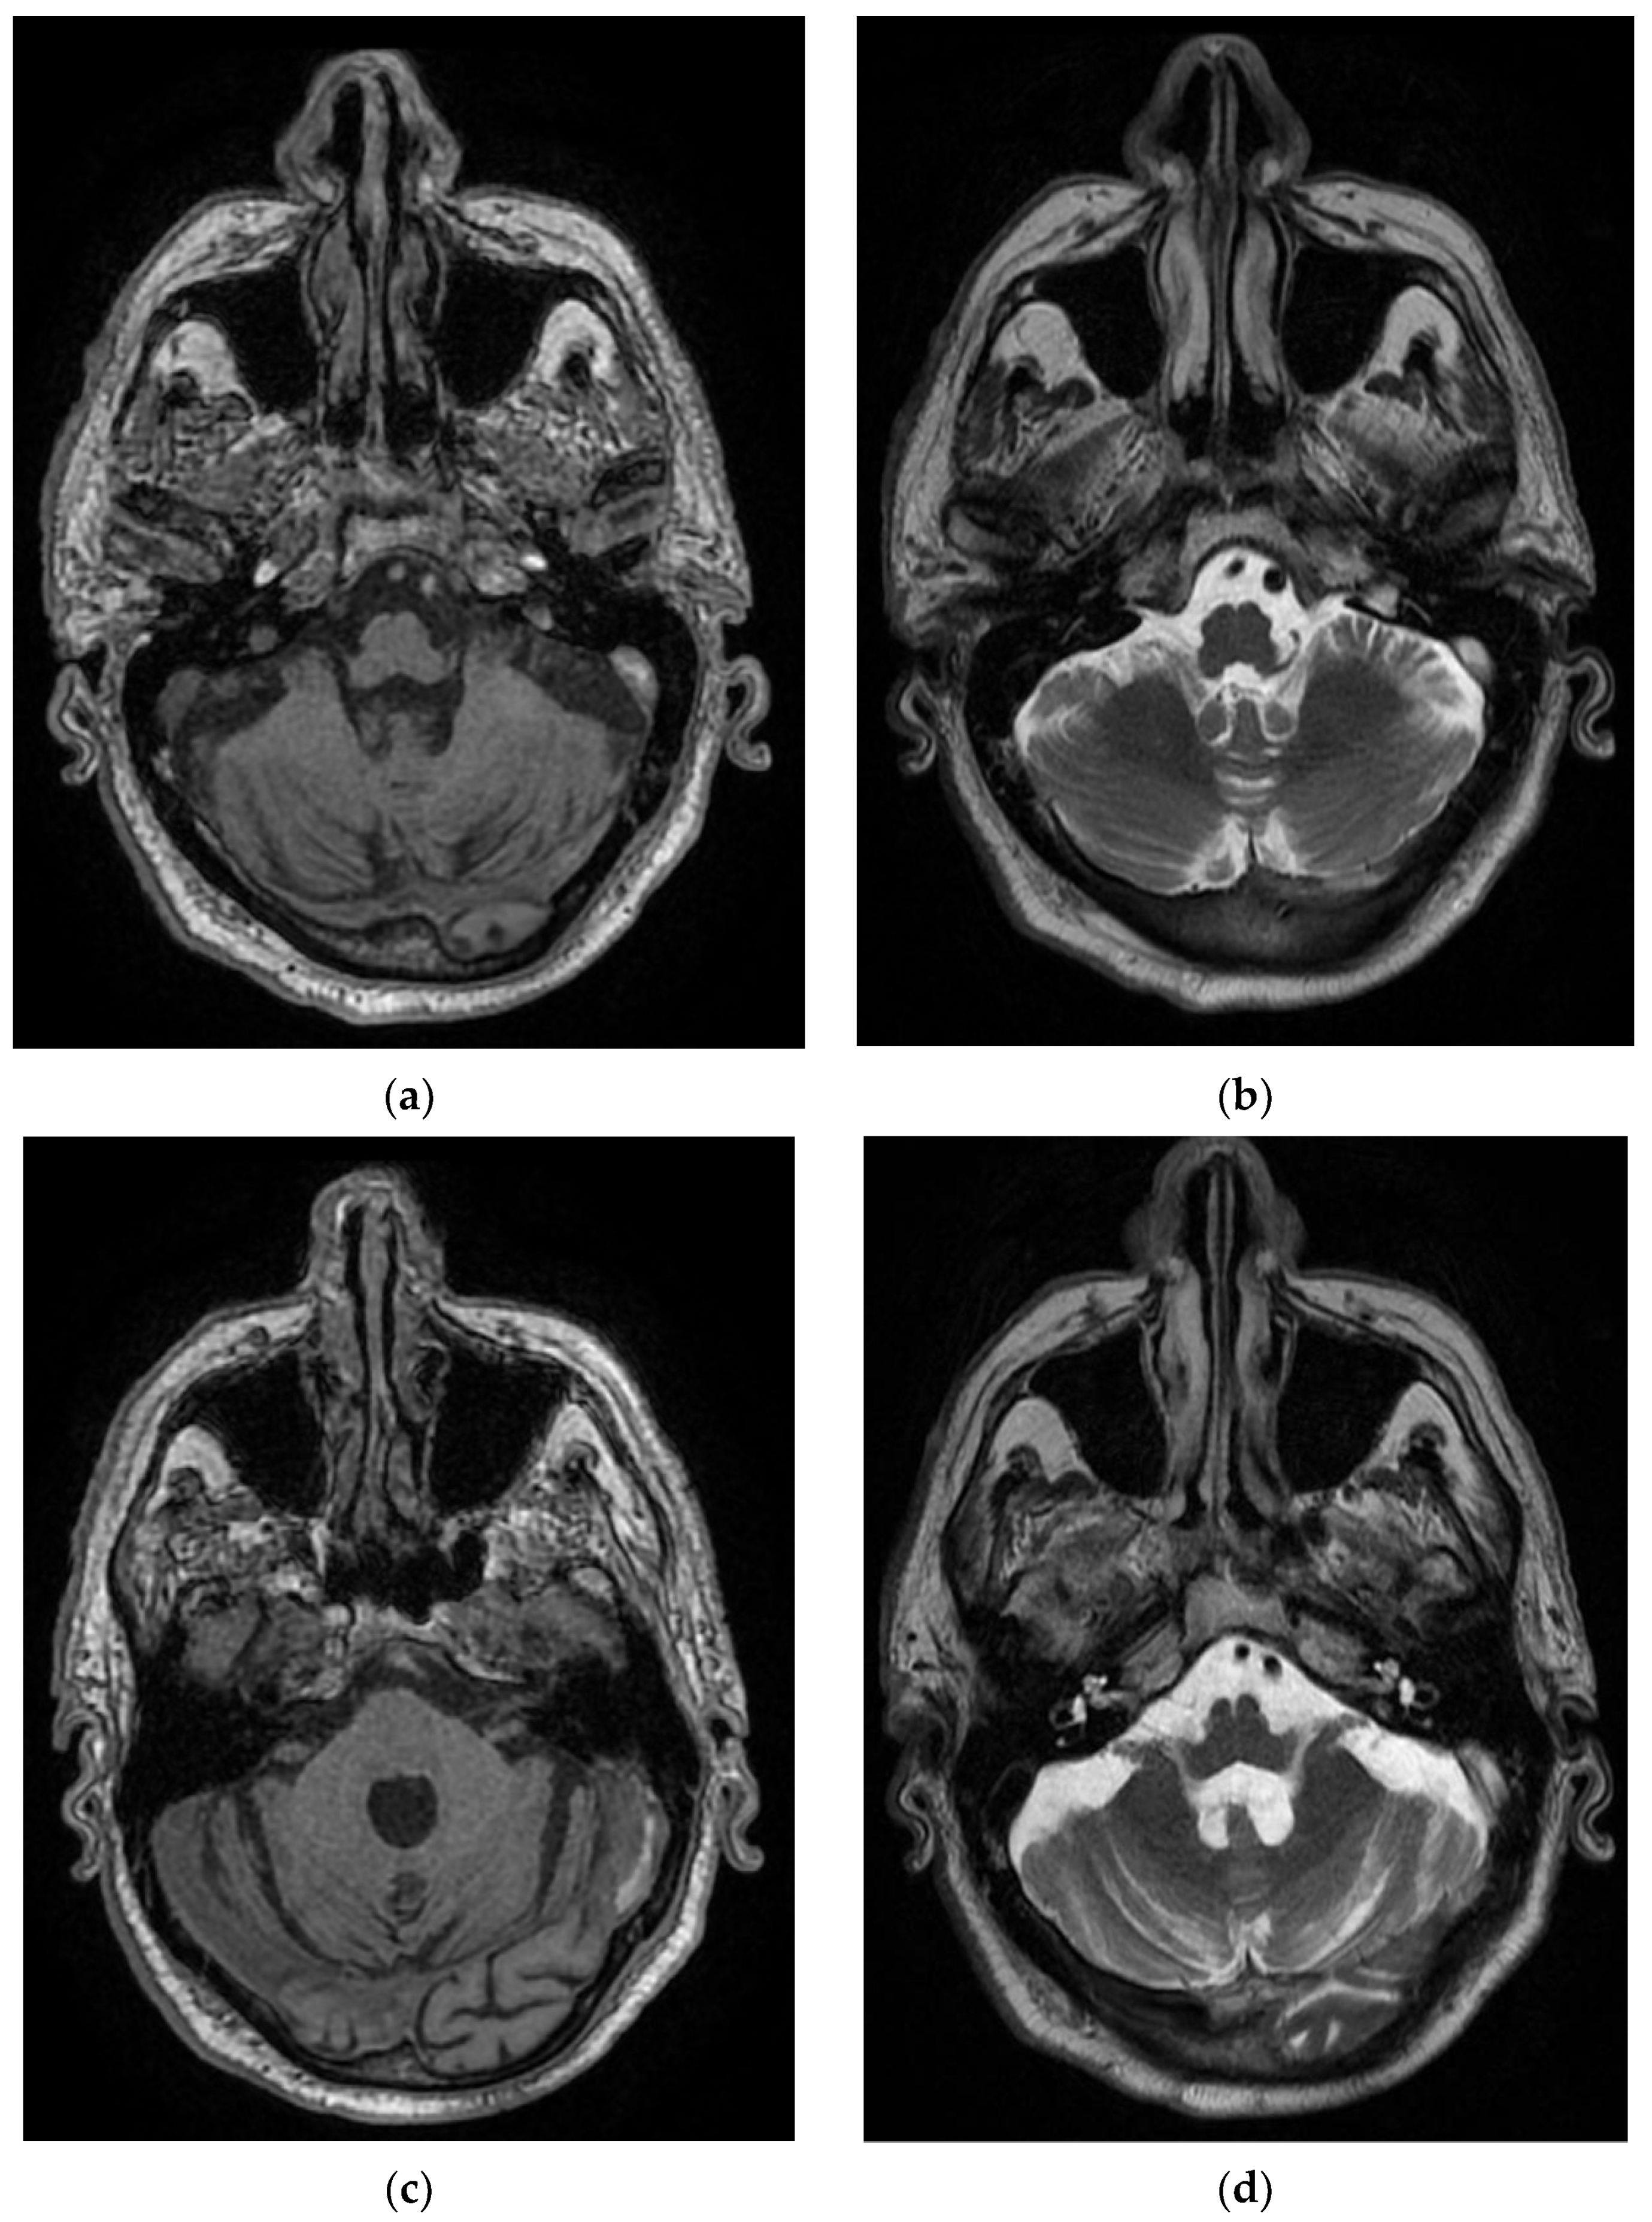

This patient, aged 66 years, presented to the emergency department for language disorders with fluctuating evolution. Neurological objective examination on admission showed the patient to be conscious, cooperative, with no motor deficits, lower limb ataxia, and bilateral plantar–indifferent cutaneous reflex. During hospitalization, he underwent a diabetes consultation, after which insulin therapy was initiated, a carotid Doppler echo, showing bilateral carotid atheromatosis, an EMG, which showed predominantly sensory axonal polyneuropathy, a cervical–thoracic spine MRI which showed T7–T9–T10 intraspongious herniation and a C5–C6 disc overhang; there was also a C6–C7 protrusion with left C7 radicular conflict, and a brain MRI evidencing T1–T2 nonhomogeneous hyperintense material partially occupying the transverse sinus and left–sided sigmoid sinus, with extension to the jugular bulb–left transverse–sigmoid–jugular venous subacute thrombosis (Figure 6).

Figure 6. Hyperintense and nonhomogeneous T1 and T2 material, in the Case 6 patient, which partially occupies the transverse sinus (a,b) and left sigmoid sinus (c,d) towards the jugular bulb (e,f)–left venous transverse–sigmoid–jugular subacute thrombosis.